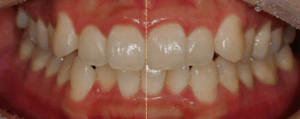

삐뚤빼뚤한 치아, 윗니가 아랫니를 많이 덮는다면? 비발치 교정으로 해결한 총생 & 과개교합 케이스

안녕하세요, 교정과 전문의 김정은입니다. ​ 오늘 제가 알려드릴 내용은 치료가 필요한 부정교합(malocclusion)은 도대체 무엇인가에 대해 알려드리면서 이와 관련된 케이스를 활용해 해결 과정을 소개해 드릴까 합니다. ​ 먼저, ​malocclusion에 대해 설명해…